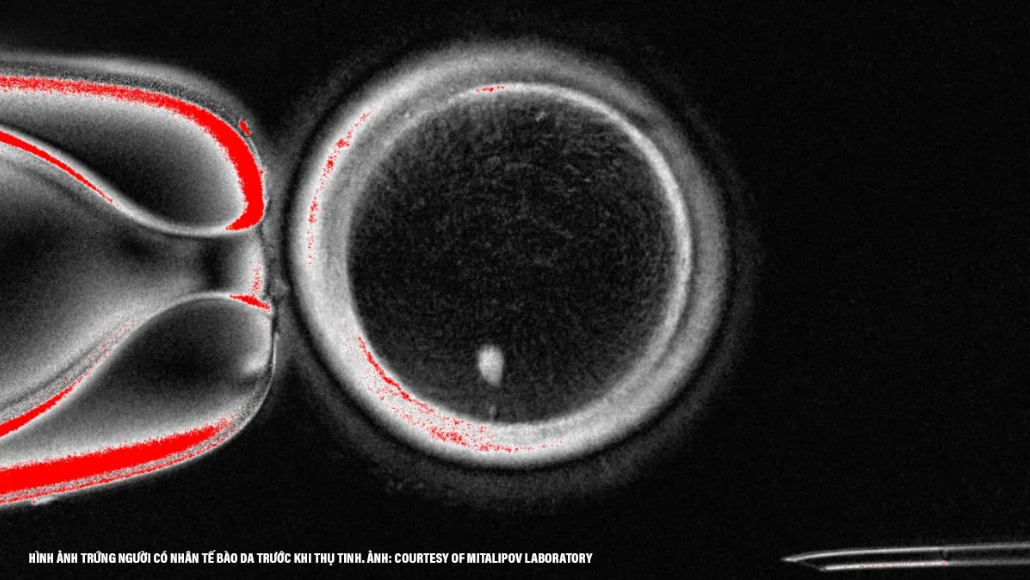

Old  Default Khoa học đã tạo ra trứng người từ tế bào da và đem sử dụng chúng để hình thành ra phôi thai

Các khoa học gia ở Mỹ vừa cho công bố ra một bước đột phá gây ra nhiều tranh cãi trong lãnh vực sinh sản: họ đã tạo ra trứng người từ tế bào da và thậm chí còn cho thụ tinh được để hình thành ra phôi thai ở giai đoạn sớm. Công trình này, do nhóm chuyên gia nghiên cứu tại Đại học Y khoa ở tiểu bang Oregon thực hiện và đăng tải lên tạp chí Nature Communications, mở ra triển vọng mới về một thế hệ kỹ thuật điều trị bệnh vô sinh mới, nhưng đồng thời kéo theo nhiều câu hỏi về mặt đạo đức.

Trong cuộc thí nghiệm, nhóm đã lấy nhân của tế bào da người và cấy vào một trứng được hiến tặng đã loại bỏ ra nhân. Kỹ thuật này gợi nhớ đến phương pháp từng tạo ra con cừu Dolly nổi tiếng hồi năm 1997. Sau đó, trứng được kích thích qua xung điện và thuốc để bắt chước quá trình cho giảm phân, nhằm loại bỏ bớt bộ nhiễm sắc thể. Kết quả, họ đã thu thập được 82 trứng có thể cho thụ tinh.

(Minh họa)